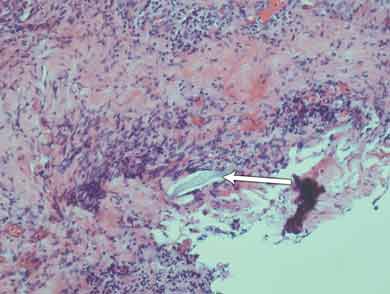

Histological results of the initial surgical specimen showed a small foreign body several microns in length intimately associated with deeply placed active inflammation (Box 1). There was fibroproliferative activity and an infiltrate of inflammatory cells; these were associated with tissue necrosis and microabscess formation. Culture of a preoperative conjunctival swab was negative for microbial growth.

The original foreign body extracted during surgery was compared with a specimen of crayfish antennae and was found to be similar to the very outer layer (1–2 μm) of the specimen (Box 2). It most likely became lodged while the patient was handling crayfish or cleaning the crayfish tank without eye protection, which he was doing extensively during the morning that the red eye developed. The crayfish caught in this area are of several different types, although the Panulirus ornatus (tropical rock lobster) make up 95% of the local population.1